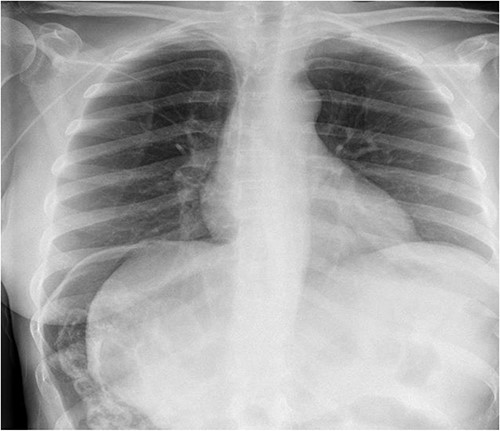

A 49-year-old female with a background of stage IV diffuse large B-cell lymphoma and subsequent chronic graft-versus-host disease (cGVHD) from a bone marrow transplant presented to a rural referral hospital in New South Wales with a 12-h history of painless per rectal bleeding and fever. She had undergone her last cycle of chemotherapy 12 months prior and her cGVHD was being treated with dexamethasone mouthwash, oral cyclosporine and an infusion of rituximab, administered the day prior to this presentation. On examination she had a soft, but distended abdomen. Laboratory investigations revealed thrombocytopenia and hypokalaemia. Computed tomography (CT) of the abdomen and pelvis had a bizarre appearance due to pneumatosis cystoides coli extending from the ileocaecal junction to the mid-transverse colon (Figs 1–3). A chest X-ray was also taken, which shows evidence transmural air within the ascending colon, including the hepatic junction (Fig. 4). Given her benign abdominal examination, her management was initially supportive with intravenous antibiotics, intravenous fluid resuscitation and correction of electrolyte abnormalities. She was subsequently transferred to a metropolitan tertiary hospital, under her usual treating haematologist with consultation by the colorectal surgical team. She recovered and did not require any acute surgical intervention for pneumatosis cystoides coli.